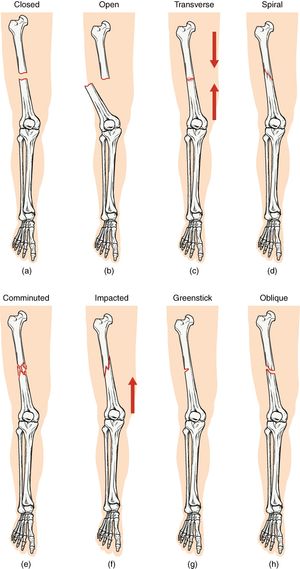

(a) 폐쇄 골절

(b) 개방 골절

(c) 가로 골절

(d) 나선 골절

(e) 분쇄 골절

(f) 압박 골절

(g) 불완전 골절

(h) 사선 골절

정형외과 의학에서 골절은 다양한 방식으로 분류된다.골절은 추가적으로 이동할 가능성에 따라 안정형과 불안정형으로 나눌 수 있다.

- 선상 골절 – 뼈의 긴 축과 평행한 골절

- 횡 골절 – 뼈의 긴 축에 직각인 골절

- 사선 골절 – 뼈의 긴 축에 대각선인 골절(30° 이상)

- 나선 골절 – 뼈의 적어도 한 부분이 꼬인 골절

- 압박 골절/쐐기 골절 – 보통 척추에서 발생하며, 예를 들어 척추뼈의 앞부분이 골다공증으로 인해 무너지는 경우(외상 유무에 관계없이 뼈가 부서지기 쉽고 골절되기 쉬운 의학적 상태)

- 충격 골절 – 뼈 조각이 서로 밀려 들어갈 때 발생하는 골절

; 가로 골절

: 골절선이 뼈의 장축에 대해 거의 직각을 이루는 골절을 말한다.

; 세로 골절

: 골절선이 뼈의 장축에 대해 거의 평행을 이루는 골절을 말한다.

; 사선 골절

: 골절선이 뼈의 장축에 대해 비스듬하게 되어 있는 (거의 직각도 평행도 아닌) 골절을 말한다.

; Spiral fracture영어

: 골절선이 뼈의 장축에 대해 나선형으로 되어 있는 골절을 말한다.